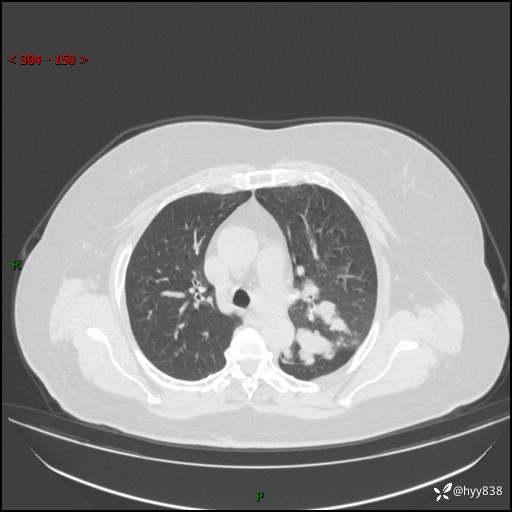

老年女性,左上肺结节8年。典型又不典型,看你如何解读---结果公布(值得分析)

主诉:检查发现左上肺结节8年,较前增大。

简要病史:患者于8年前体检行胸部CT检查发现左上肺结节(4mm),患者平素间断咳嗽咳痰,无心慌、胸闷、胸痛、呼吸困难、低热、盗汗,无头痛、头晕,无腹痛、腹胀等不适,未行特殊处理,定期复查。2023-09-21胸部CT示左上肺结节(2cm)较前增大,2024-02-01胸部CT示左上肺尖后段(39*32mm),左侧肺门及纵隔淋巴结增大,现患者欲求手术治疗,遂来我院就诊,以“左上肺结节”收入我科。 患者自起病以来,精神可,睡眠可,饮食可,大小便正常,体重无明显改变。

辅助检查:CT

增强(动脉期+静脉期)